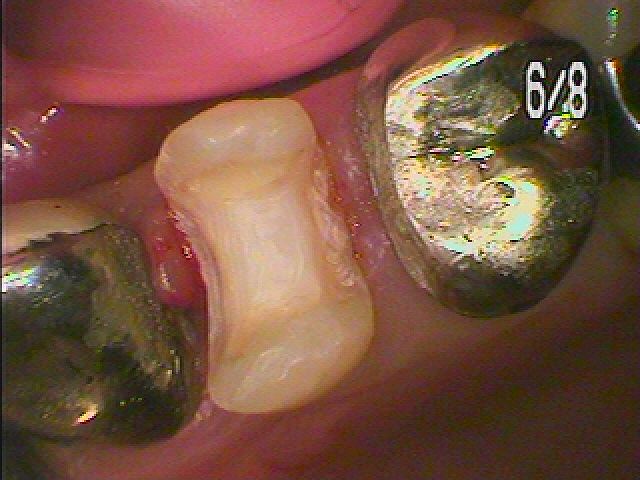

左上4番の銀歯を外していきます 銀歯の下は大きく虫歯になっていることがあります|お知らせ |広島市安佐南区の歯科医院 左上4番の銀歯を外していきます 銀歯の下は大きく虫歯になっていることがあります トップ お知らせ・ブログ お知らせ 左上4番の銀歯を外していきます 銀歯の下は大きく虫歯になっていることがあります 左上4番の銀歯を外していきます 銀歯の下は大きく虫歯になっていることがあります この銀歯を外していきました 銀歯を外した直後になります 中は大きく虫歯になっています 中はこのように大きく虫歯になっていました CR樹脂にて覆罩を行い型取りを行っていきます 側面から セレックプライムスキャンを用いたセラミック治療へ このようにきれいなセラミックが入りました 喜んでいただきました Web診療予約 初めての方へ 選ばれ続ける理由 院内設備について 歯が痛いしみる一般歯科 歯がぐらぐらする歯周病 健康な歯を保ちたい予防歯科 子供の虫歯予防をしたい小児歯科 銀歯をセラミックに審美歯科 白い歯を目指しませんか?ホワイトニング 矯正専門医がいるので安心矯正歯科 抜けた歯を補いたいインプラント・入れ歯 医院案内 スタッフ紹介 メリィハウス歯科クリニックオフィシャルホームページ ラベンダー歯科クリニックオフィシャルホームページ お知らせ・ブログ ホーム 診療科目 一般歯科 歯周病治療 予防治療 小児歯科 審美治療 ホワイトニング 矯正歯科 入れ歯・インプラント マウスピース矯正 初めての方へ 院長・スタッフ 設備紹介 医院案内・アクセス メニューを閉じる